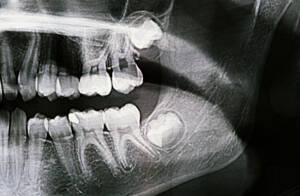

某天小美因牙痛及不能張口的問題而來就診,經臨床檢查及X光顯示,原來是下顎的阻生智慧齒作怪。因口腔空間不足,智慧齒不能順利長出。由於清潔難度增加,除了會導致牙肉發炎之外,也會引致前面大牙的局部牙周病及蛀牙問題。